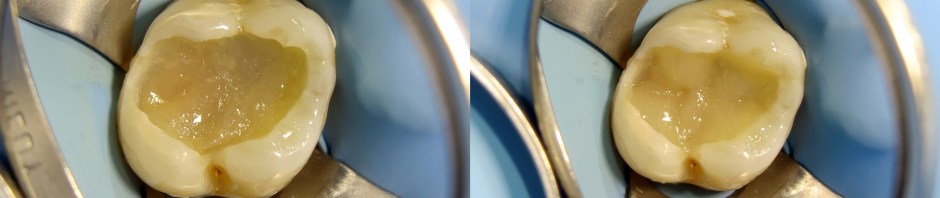

Replacing amalgam with composite resin using two shade and no tint

Yesterday, patient came with a broken, 2 years old, and improper amalgam filling on upper left first molar, which has bothered her appearance, and regularly food debris stuck at the margin, not easy to remove, causing sensitive tooth and bad breath.

1. Rubberdam placement: hu friedy rubberdam clamp and nictone rubberdam sheet. (Double high suction was used to suck amalgam debris after removal)

2. Filtek bulkfill flowable (3M) as first layer to make a good marginal adaptation.

3. Ever-X (fibre reinforced composite resin from GC), 2 mm.

4. G-Aenial (GC) shade A3 as a dentin color.

5. G-Aenial (GC) shade A1 as enamel color.

6. Finishing and polishing: regular arkansas stone, soflex (3M), and Enhance (Dentsply)

No tint nor color modifier was used, and now we are waiting for rehydration..